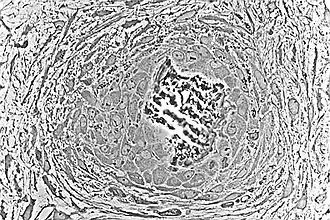

![]() Osteoblasts (purple) rimming a bony spicule (pink - on diagonal of image). In this routinely fixed and decalcified (bone mineral removed) tissue, the osteoblasts have retracted and are separated from each other and from their underlying matrix. In living bone, the cells are linked by tight junctions and gap junctions, and integrated with underlying osteocytes and matrix H&E stain. | |

Morphology and histological staining

Hematoxylin and eosin staining (H&E) shows that the cytoplasm of active osteoblasts is slightly basophilic due to the substantial presence of rough endoplasmic reticulum. The active osteoblast produces substantial collagen type I. About 10% of the bone matrix is collagen with the balance mineral.[29] The osteoblast's nucleus is spherical and large. An active osteoblast is characterized morphologically by a prominent Golgi apparatus that appears histologically as a clear zone adjacent to the nucleus. The products of the cell are mostly for transport into the osteoid, the non-mineralized matrix. Active osteoblasts can be labeled by antibodies to Type-I collagen, or using naphthol phosphate and the diazonium dye fast blue to demonstrate alkaline phosphatase enzyme activity directly.

Light micrograph of decalcified cancellous bone displaying osteoblasts actively synthesizing osteoid, containing two osteocytes -